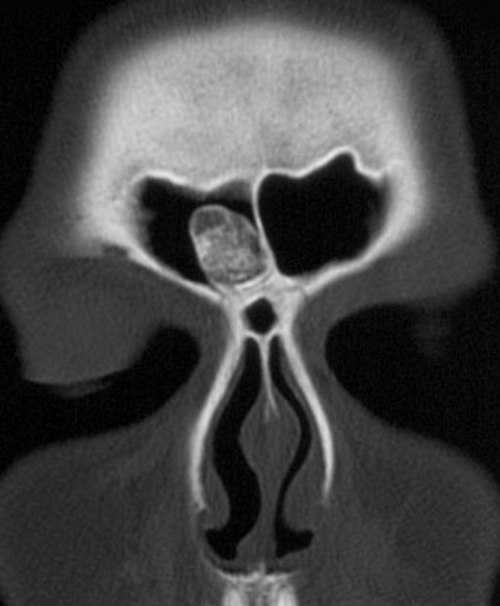

Clinical signs of Paget disease of the bone include:

- Hearing loss

- Enlarging head size (having to obtain bigger hats)

- Bone pain

- Microfractures

Patients older than 40-years-old are more likely to have isolated increased alkaline phosphatase, which is the most prevalent cause of isolated raised alkaline phosphatase.

Patients with Paget disease of the bone also tend to have lion-like facies with involvement of the craniofacial bones.